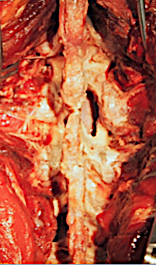

La descompresión interlaminar está indicada en el tratamiento de la estenosis de canal lumbar, una patología con elevada incidencia y prevalencia. Técnicamente consiste en retirar las partes blandas que separan ambas láminas y espinosas (ligamento amarillo, interespinoso, epiespinoso) hasta exponer el saco dural. Se puede completar con discectomía (microdiscectomía), recalibraje de receso lateral y foraminotomía bilateral.

Esqueletizacion bilateral de ambas láminas hasta facetas.